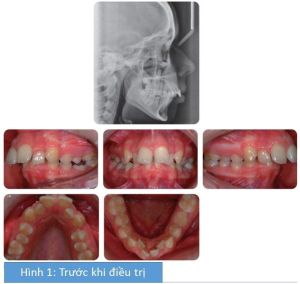

Bệnh nhân nữ 12 tuổi có sai lệch tương quan răng cửa hạng II tiểu loại I trên nền xương hạng II với kích thước dọc trung bình và chen chúc nhẹ ở cả 2 cung răng, phức tạp bởi:

- Độ cắn chìa tăng (10mm)

- R12 và R22 mọc lệch phía khẩu cái

- Thiếu R35

- R75 (răng cối sữa thứ 2 hàm dưới bên trái) mọc thấp